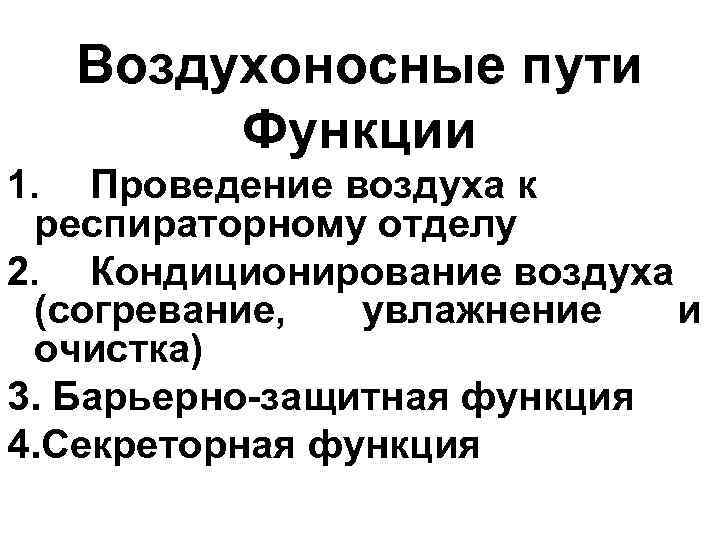

Воздухоносные пути Функции 1. Проведение воздуха к респираторному отделу 2. Кондиционирование воздуха (согревание, увлажнение и очистка) 3. Барьерно-защитная функция 4. Секреторная функция